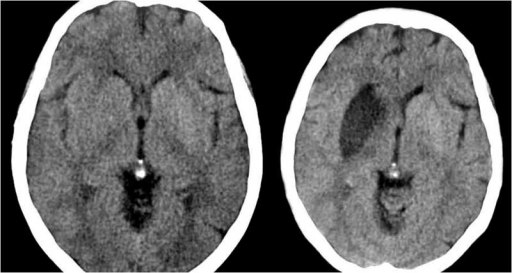

Signo visible en la TC craneal sin contraste. Fue inicialmente descrito por D.H. Yock en 1981 y corresponde a la alta densidad de la primera porción de la arteria cerebral media (ACM) comparada con la arteria contralateral, y es un signo de isquemia cerebral por oclusión arterial por trombo o émbolo, cuya densidad (80 UH=unidades Hounsfield) es más alta que la de la sangre circulante(40 UH) por la mayor cantidad de fibrina y proteínas y la menor proporción de suero.

Es un signo precoz de accidente cerebro-vascular (ACV), aparece en las primeras 6 horas y deja de verse en el ACV evolucionado, por la resolución del trombo.

Se ha visto, como falso positivo, en pacientes asintomáticos con poliglobulia o deshidratación, por el aumento del hematocrito, aunque en este caso es bilateral. En pacientes con arteriosclerosis y calcificaciones vasculares, la apariencia de la ACM puede parecer hiperdensa. También se ha descrito en algún paciente con encefalitis por herpes simplex, que característicamente afecta al lóbulo temporal.

Imagen del mismo paciente 2 días después del primer estudio. Se observan un área hipodensa por infarto en el territorio de la ACM derecha.